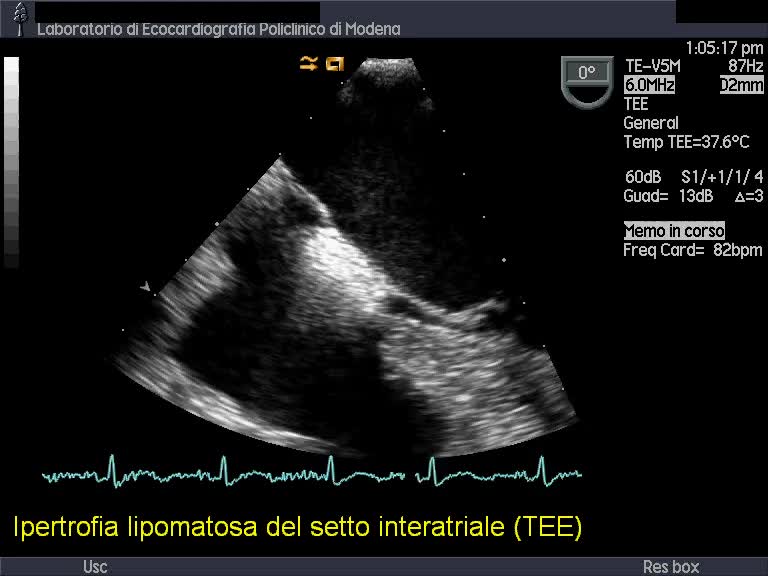

Titolo:

Ipertrofia lipomatosa del setto interatriale

Autore:

Andrea Barbieri